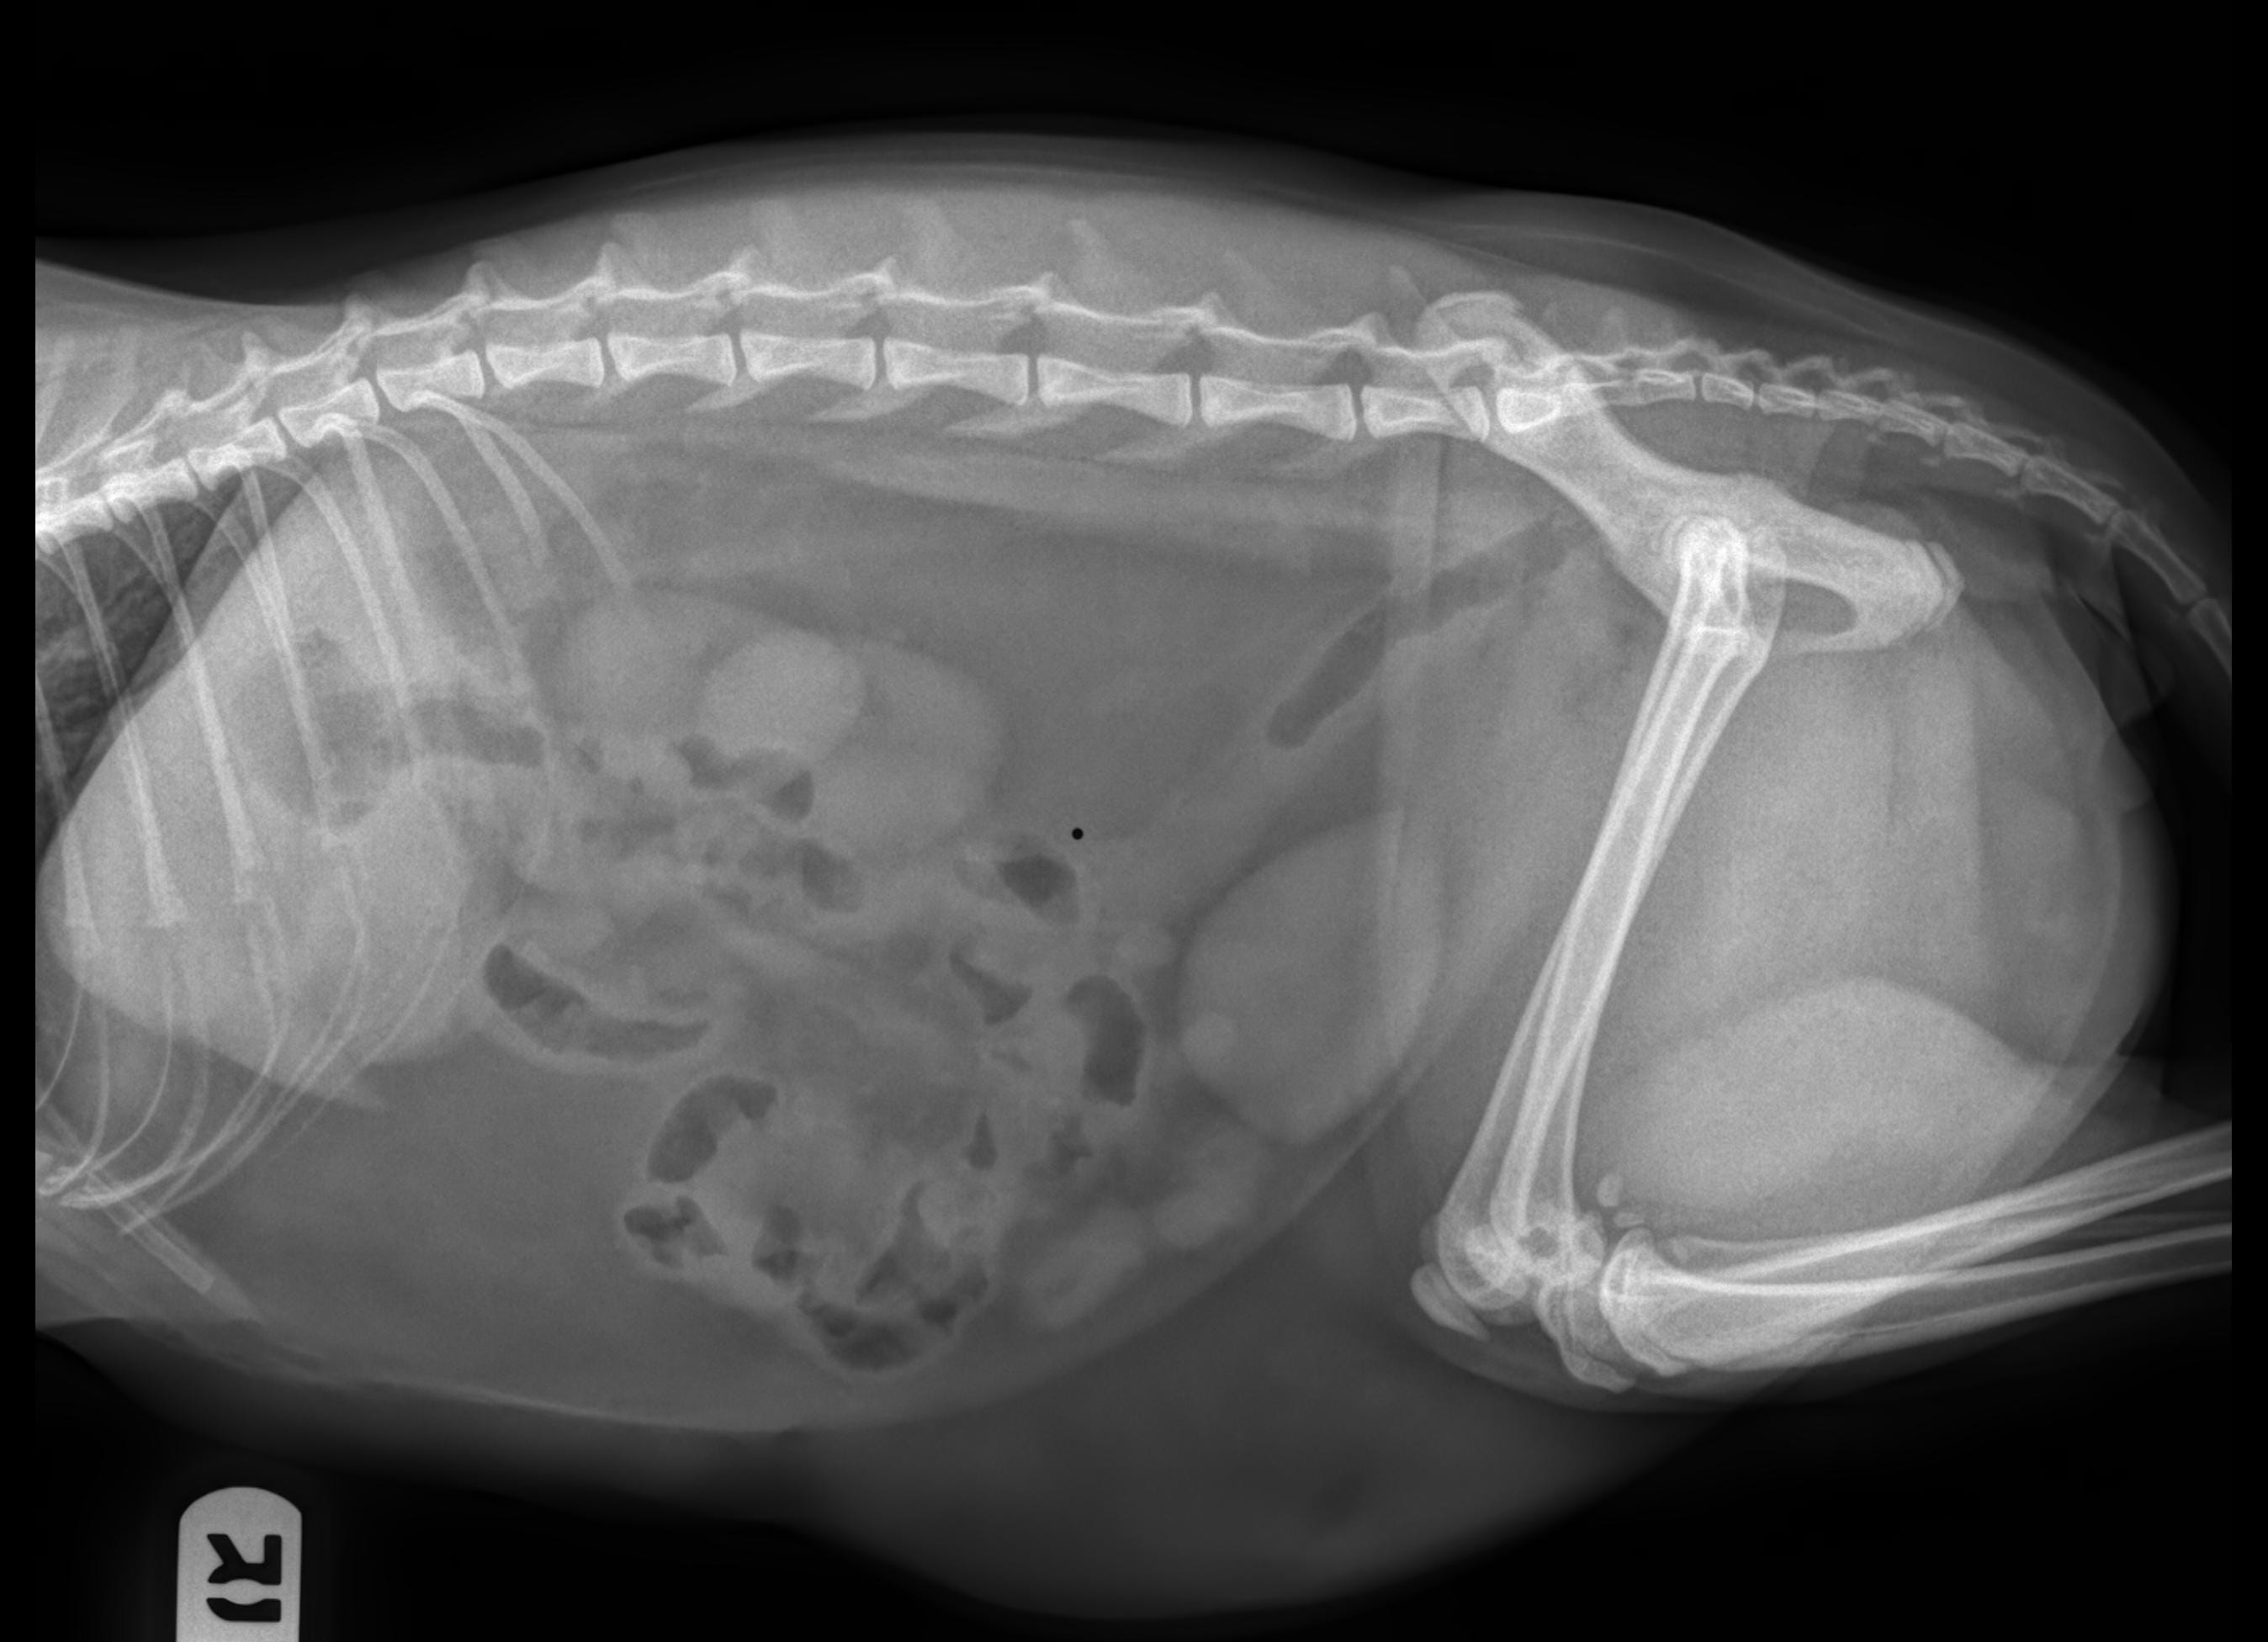

Hi, my cat is considered having a foreign body inside his abdomen. On the 1st day, he vomited alot so I took him to vet and after medication he stop vomiting but still acted abnormal. He has been losing his appetide 4 days, and he doesnt want to drink either. I dont see he urinates or defecates by himseft, so I try to help him by using enema to push all the poop inside him out and squeezing his bladder to help urinate. Now is 4th day, he drools constantly and I dont know what to do. Please help

I'm sorry to hear that Bo is feeling so poorly. A foreign body intestinal and/or stomach obstruction will cause vomiting and nausea (drooling is a sign of nausea), a loss of appetite and lethargy. Foreign body obstructions require surgery and supportive fluids and medications for treatment. Without surgical removal of the foreign material, the intestinal wall will become severely diseased and perforate, causing intestinal contents to leak into the abdomen, causing severe infection (sepsis) which is life-threatening. Since Bo is doing so poorly, I strongly recommend taking him to the emergency vet immediately for evaluation and likely surgery. Do not give additional enemas or squeeze his bladder without direct veterinary guidance. Some over the counter enemas (such as Fleet enemas) are toxic for cats. Squeezing his bladder could also cause an intestinal perforation if the intestines are diseased from the foreign material. I hope that all goes well.